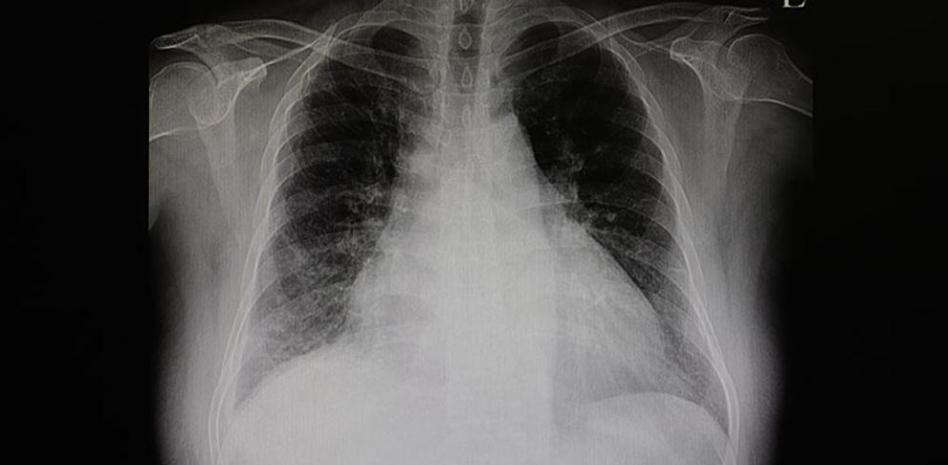

«El cardiólogo hará diferentes pruebas que incluyen una radiografía de tórax, un electrocardiograma, un ecocardiograma y el uso de un monitor Holter».

Cuando se registra insuficiencia cardíaca con frecuencia la sangre retrocede. El líquido, entonces, se puede acumular en los pulmones.